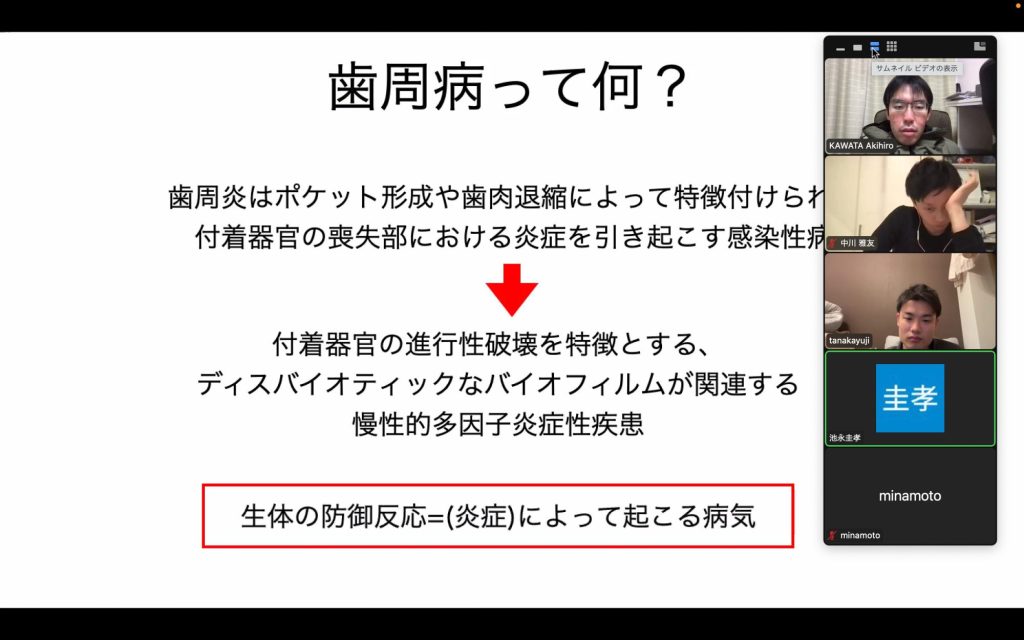

もう一つは歯周病についての内容でした。

もう一つは歯周病についての内容でした。